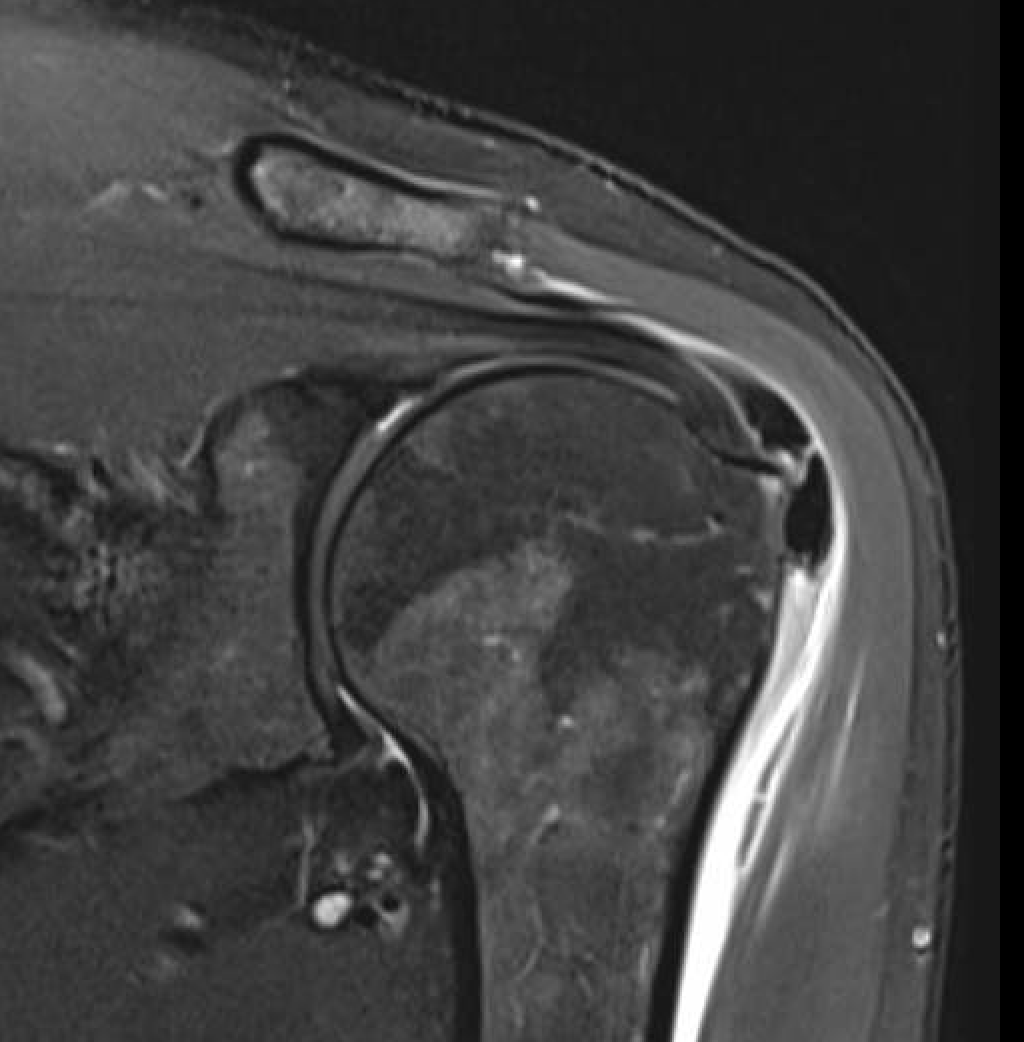

MRI

Calcium has low signal intensity on all sequences